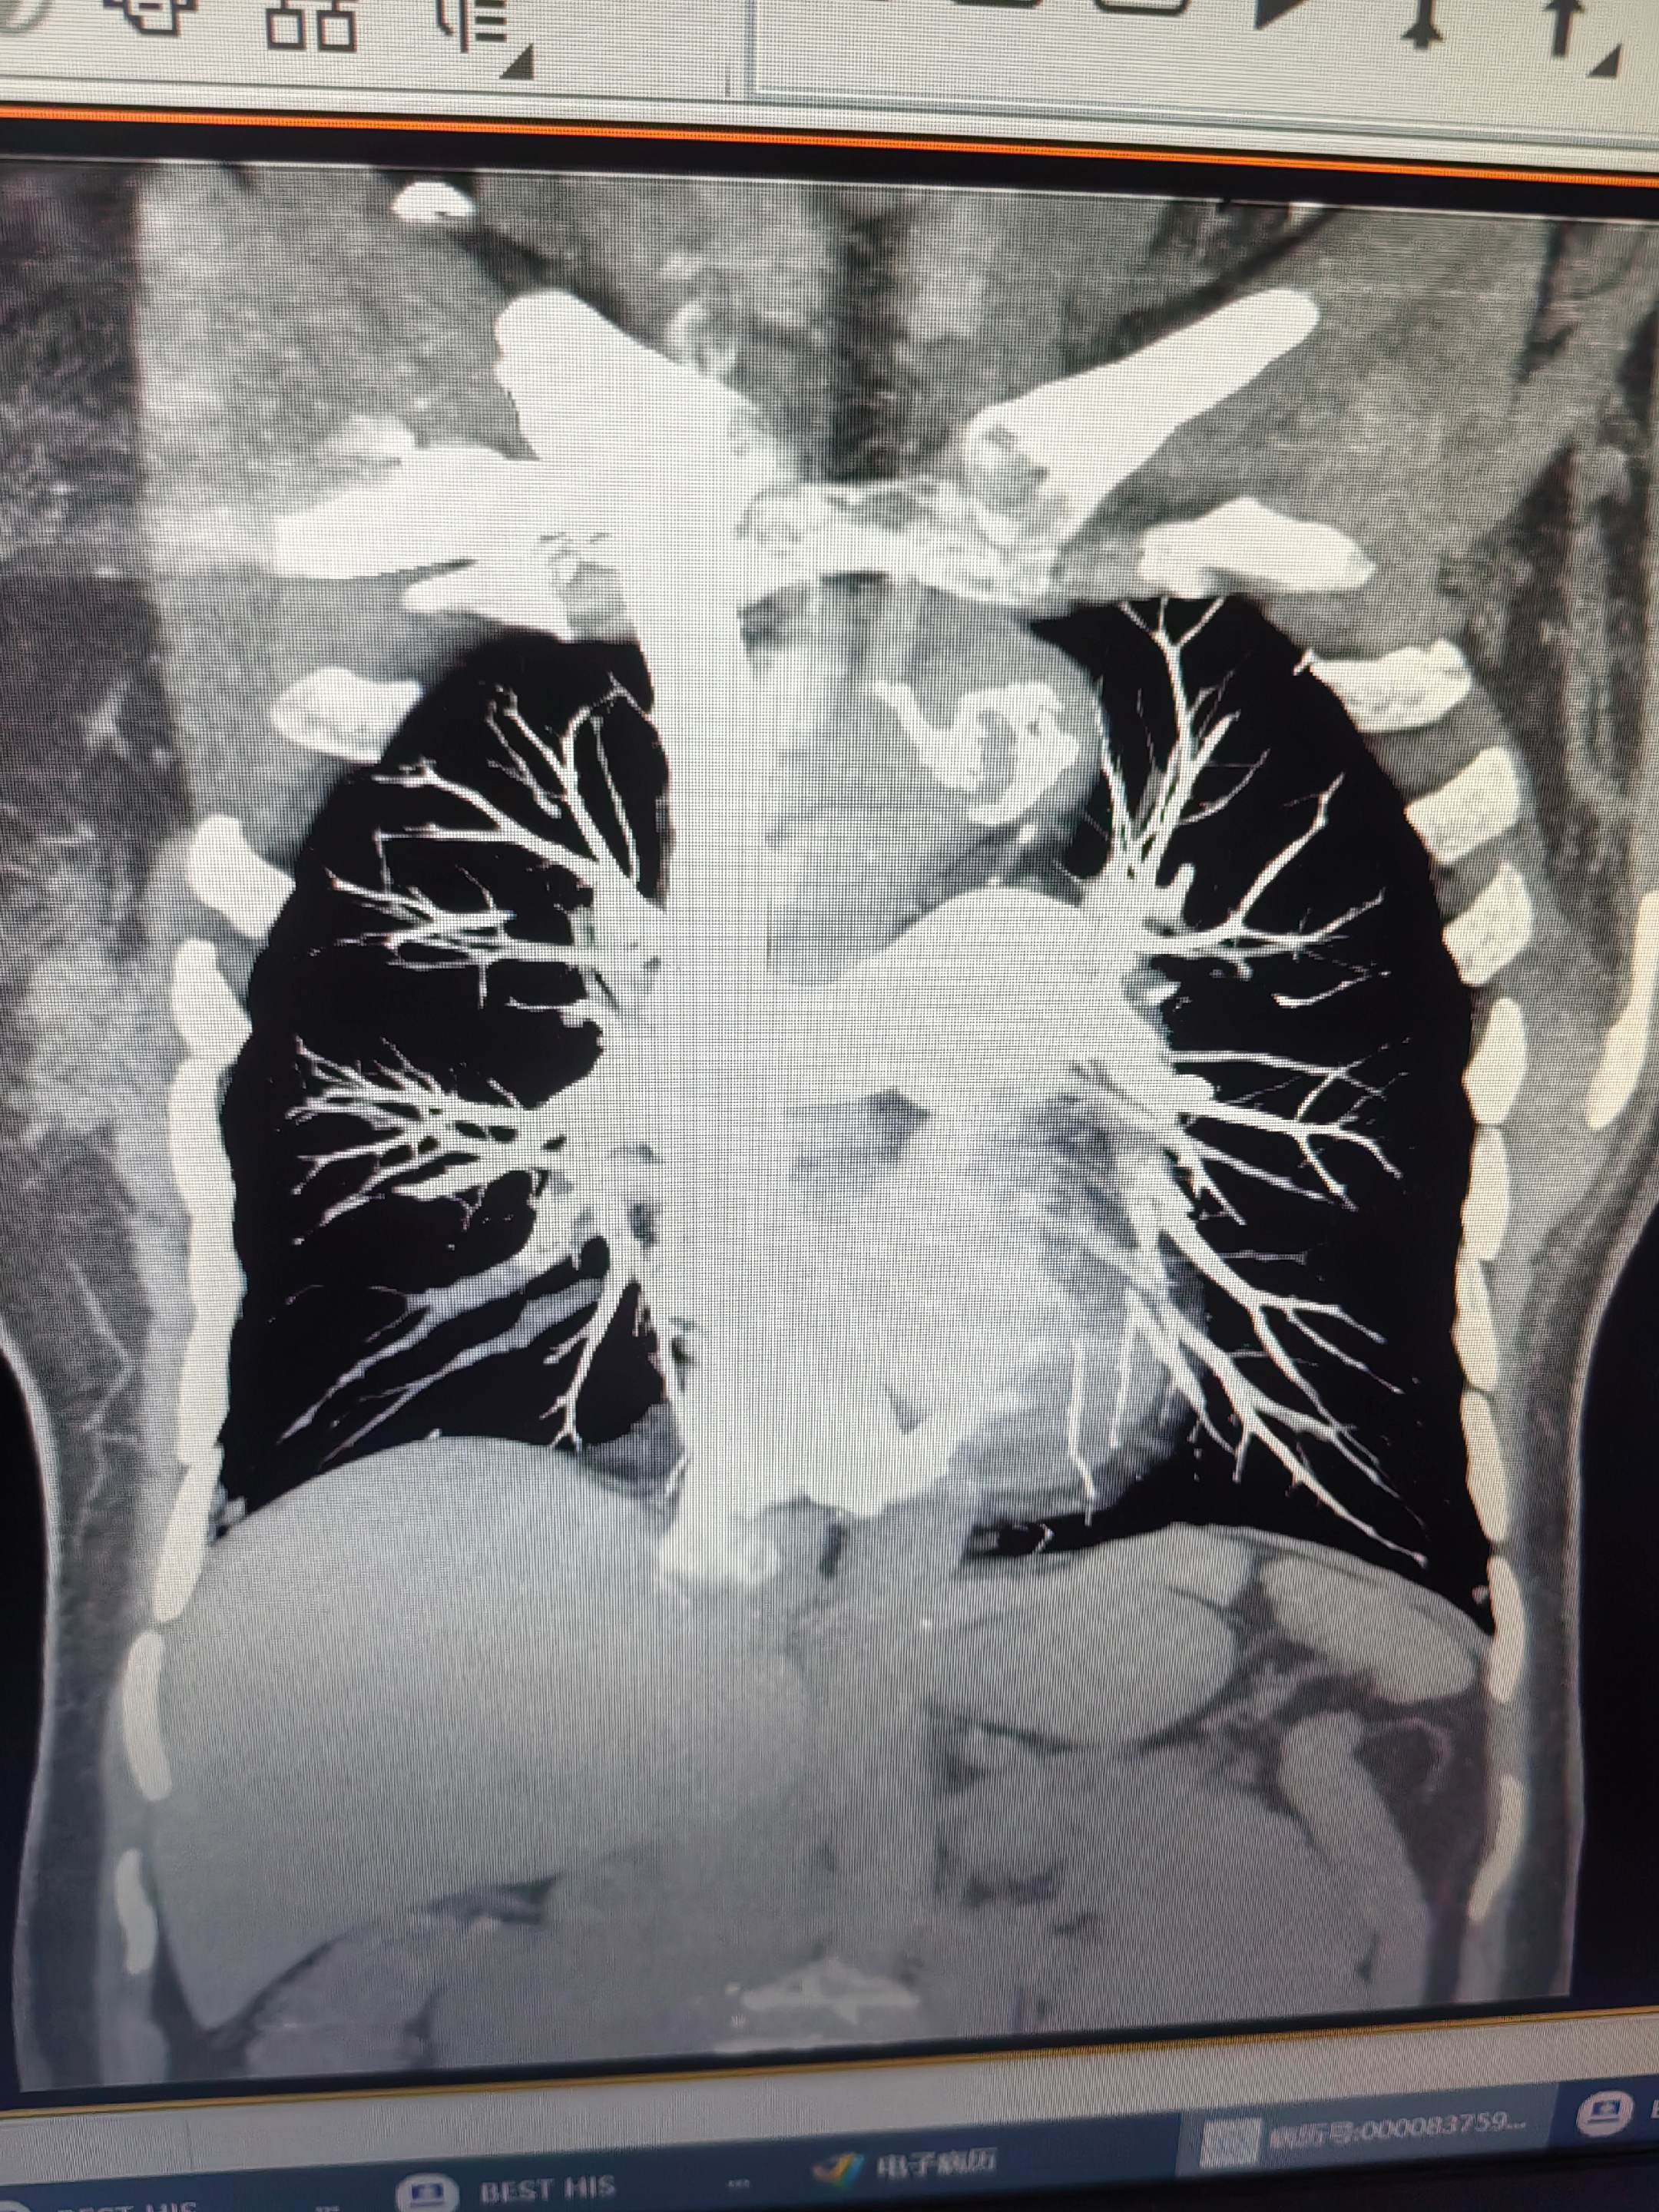

肺栓塞。